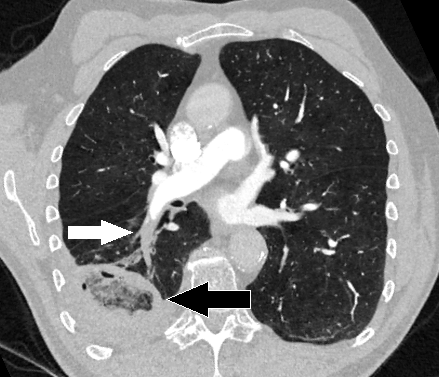

Pulmonary Embolism (White Arrow) with Infarcted Lung (Black Arrow)